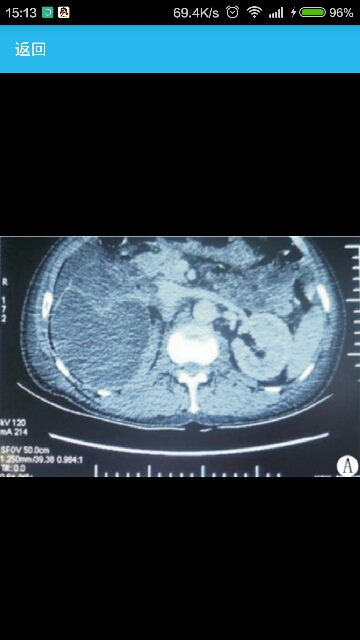

右侧腰部间断性疼痛2年余,突发高热3周。 入院查体:体温39℃,右侧腰部扪及包块,边界不清,右肾区叩击痛阳性。B超示右肾形态失常,肾内积液,合并有混杂密度,可见分隔,右侧输尿管结石。入院后进一步行CT检查提示右侧输尿管结石并右肾重度积水,内见混杂密度影(图1)。